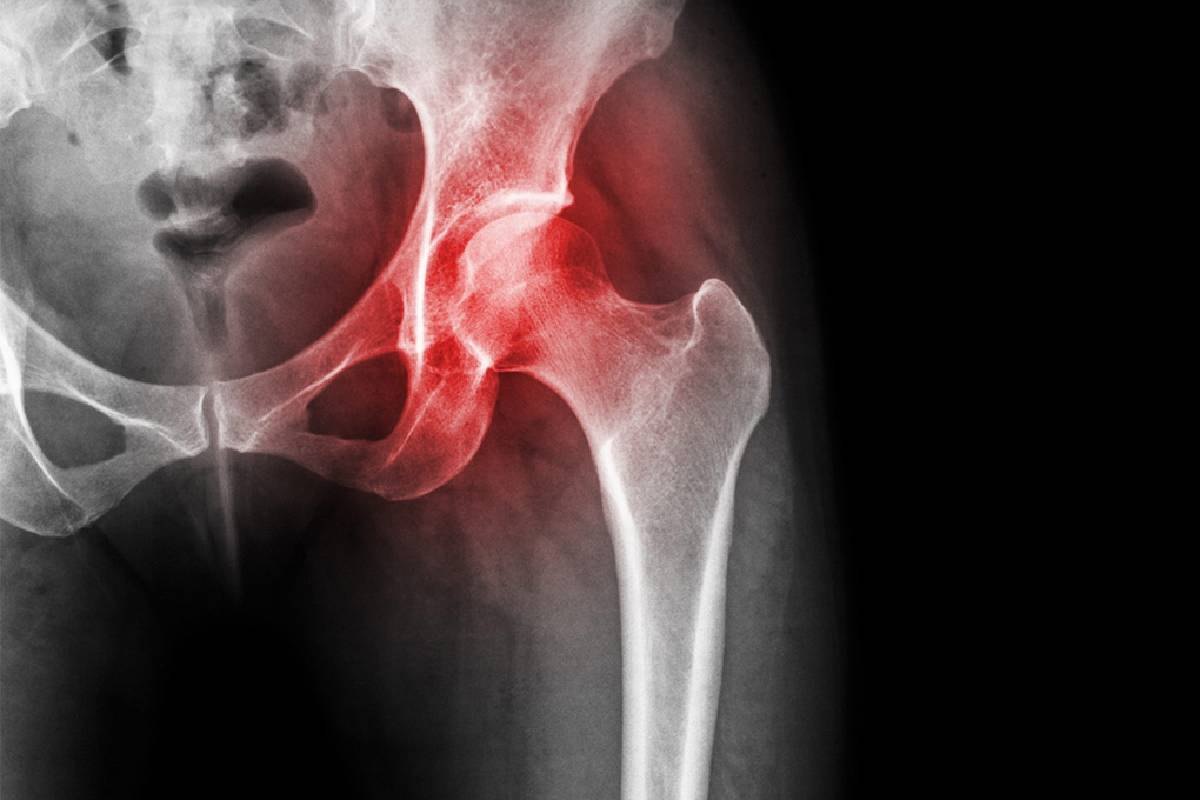

نکروز آواسکولار سر استخوان ران، که در زبان عامیانه به سیاه شدن سر استخوان ران شناخته می‌شود، یک بیماری جدی استخوانی است که می‌تواند زندگی روزمره افراد را تحت تأثیر قرار دهد. این عارضه زمانی رخ می‌دهد که جریان خون به سر استخوان ران کاهش یافته یا قطع شود، که منجر به مرگ سلول‌های استخوانی و آسیب به مفصل ران می‌گردد. در این مقاله، به بررسی کامل این بیماری، از تعریف و علل تا علائم، تشخیص و درمان می‌پردازیم تا درک بهتری از آن به دست آورید.

نکروز سر استخوان ران یا استئونکروز، وضعیتی است که در آن خون‌رسانی به قسمت بالایی استخوان ران، یعنی سر استخوان فمور، مختل می‌شود. این اختلال باعث مرگ بافت استخوانی می‌گردد و در نهایت می‌تواند منجر به فروپاشی استخوان و آسیب به مفصل ران شود. مفصل ران یک مفصل گوی و کاسه‌ای است که سر استخوان ران (گوی) در حفره استابولوم (کاسه) قرار می‌گیرد و با غضروف پوشیده شده تا حرکت نرم و روان را فراهم کند. این بیماری نباید با مشکلات عملکردی مفصل ران مانند سندرم اسنپینگ هیپ که بیشتر با صدا دادن یا گیر کردن مفصل همراه است، اشتباه گرفته شود.

این بیماری معمولاً در بزرگسالان بین ۵۰ تا ۷۰ سال رخ می‌دهد، اما می‌تواند در سنین دیگر نیز ظاهر شود. بدون درمان مناسب، نکروز آواسکولار می‌تواند به آرتریت پیشرونده منجر شود و فعالیت‌های روزانه مانند راه رفتن یا خم شدن را دشوار کند.